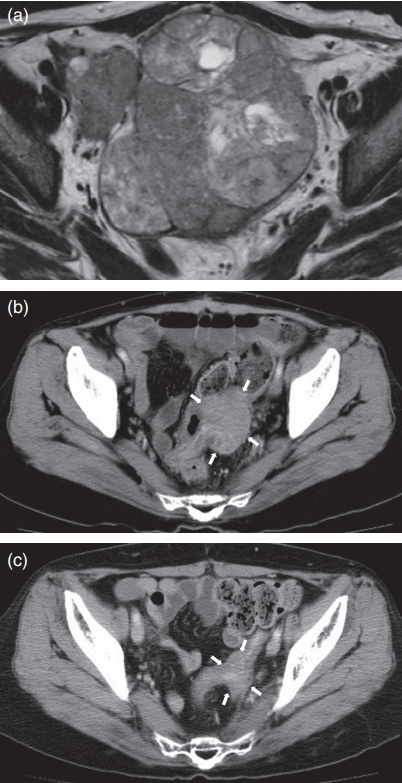

今天我们分享一例在MD安德森癌症中心寻求第二治疗意见,并通过质子治疗+激素治疗重获新生的病例故事,这个案例展现了高危人群早期筛查、复杂病例多学科诊疗以及前沿治疗技术的重要性。